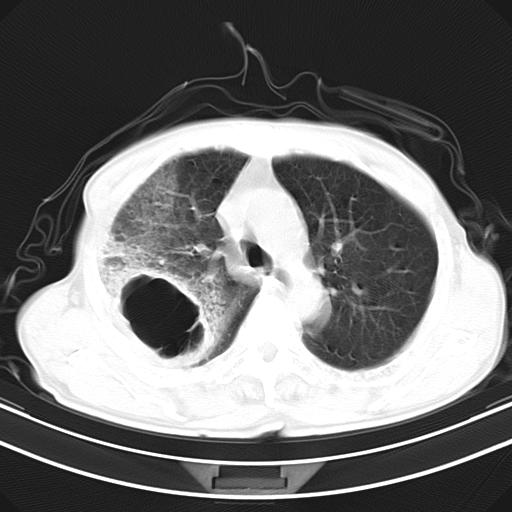

抗炎治疗10天后复查

影像所见:右上肺见一巨大厚壁空洞,内壁欠光整,右上肺广泛斑片状、大片状模糊阴影。

抗炎治疗10天后复查:右上肺模糊阴影明显减少。

诊断意见:考虑右上肺巨大含气囊肿并感染,建议继续治疗后复查。

不支持点:空腔壁较厚,欠光滑。询问病人是否有反复感染病史?

结核临床及影像,结核暂不考虑。

右肺感染性病变(右肺上叶肺脓肿?);建议:抗炎治疗后复查。

这例首先确定为感染性病变应该没问题,关键是怎么解释哪个大洞的问题。结核没有卫星病灶;脓肿没有液平;病毒感染?;真菌?;寄生虫?-----?